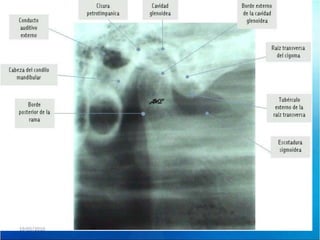

Diagnostico

PANORAMICA

RX

RESONANCIA ARTICULAR

MAGNETICA

TOMOGRAFIA

COMPUTARIZADA